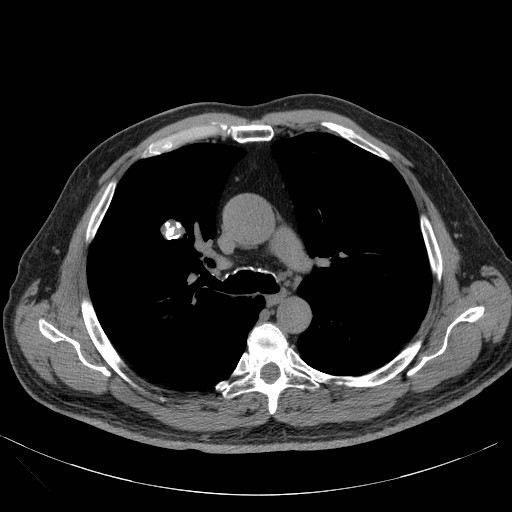

Il nodulo polmonare è un’opacità di dimensione < 3 cm, che non coinvolge la pleura, ed in genere non è associato a linfoadenopatia.

L’eziologia del nodulo polmonare può essere infiammatoria (granuloma come nel caso di TBC e sarcoidosi, ascesso), benigna (amartomi, condromi), maligna (per tumore primitivo del polmone, metastasi, linfoma o sarcoma) o da embolo settico, malformazione artero-venosa o atelettasia rotonda .

Per valutare il nodulo polmonare, vengono descritti dimensione, velocità di crescita ed alcuni aspetti morfologici :

• Densità. Può essere solida, a vetro smerigliato o parzialmente solida

• Margini. Possono essere lisci, lobulati o spiculati

• Contenuto. In caso di presenza di tessuto adiposo, calcificazioni o cavitazioni.